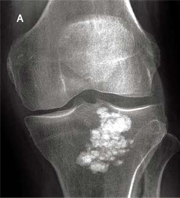

ازگود - اشلاتر osgood-schlater

(کندگی ضریح استخوان از برجستگی استخوان درشت نی)

- تعریف : بیماری ازگودشلاتر به شرایطی گفته می شود که محل اتصال تاندون کشکک به استخوان درشت نی محل التهاب و عدم یکپارچگی استخوان شود

- علائم : درد در محل اتصال به استخوان درشت نی در هنگام اعمال فشار و پس ازآن هنگامی که عضله چهارسرران در برابر مقاومت منقبض می شود، درد تحریک می شود. تورم و حساسیت در محل اتصال تاندون کشکک به استخوان درشت نی.معاینه با اشعه ایکس ممکن است وجود تکه های استخوانی و تغییرات التهابی در برجستگی درشت نی را نشان دهد.

- درمان : فرد باید استراحت کند.از گرمای موضعی و نگهدارنده های گرما استفاده کند.از اجرای حرکتهایی که موجب تحریک درد می شود نیز اجتناب کند.